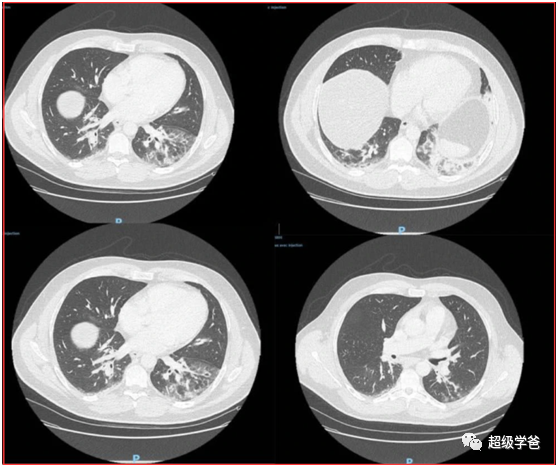

下图中,彩色的菱形方块,表示97份法国病毒样本序列,不同颜色表示来自法国不同行政区。紫色的正方形,是3份阿尔及利亚病毒序列。

除此之外,黑色的图形表示338份全球公开序列。其中*表示来自亚太地区的病毒样本序列,黑色正方形表示来自非洲的病毒样本序列,黑色实心圆表示来自北美的病毒样本序列。

横轴是时间轴,图块所在位置就是取样日期,图块左边的黑色线段的长度,表示最近的共同祖先的推断日期,离得越近就越是近亲。

最上边的蓝色菱形方块儿(G1583),是取自法国东南部并有意大利旅行史的确诊患者,与法国北部完全不同,但和意大利的毒株是近亲。

另外两例取自法国东南部并有意大利旅行史的毒株(B2340和B2334)很接近,也跟意大利的毒株类似,但跟法国北部大流行的毒株没有关系。

而法国1月底来自中国的确诊患者(IDF0372,IDF0373),其单核酸多态性G22661T是独有的,与法国的主要流行的病毒基因不同。

由此可见,法国新冠病毒疫情的毒株是一个大家族,跟中国和意大利流行的病毒并非来自同一毒株,虽然祖先一样,但早已属于不同分支。

大家关心的是,美国和美洲的样本毒株,跟武汉和法国有没有关系。图中实心黑色圆球表示美洲的样本,样本总量不大,但足以说明问题。

美洲的毒株样本可以分为三类,第一类可以跟来自亚太的毒株追溯到同样的祖先,下图中蓝色线头附近那个家族,共有7个。

需要注意的是,美洲这些毒株样本,虽然跟亚太地区的毒株是近亲,但是美国揭盖晚(3月13日才开始),这些样本有5例取自最早的输入性病例,包括撤侨。

也就是说美国的大流行,跟亚太输入病例并没有太大关系(得益于得益于美国对亚洲的严防死守)。

第二类,跟法国或欧洲其他国家的毒株有共同的祖先,这样的样本共有37例。下图中椭圆形中的实心圆球。

第三类,一个杆子杵到底,追溯到去年12月17日也没找到祖先,这样的毒株样本共有10例(红色箭头那个家族)。

所以我的结论,美国的疫情最为复杂,集齐了所有的毒株。其中庞大的两支,一支跟欧洲有关联,另一支是独立发展出来的,接下来就看美国和法国谁的疫情更早。